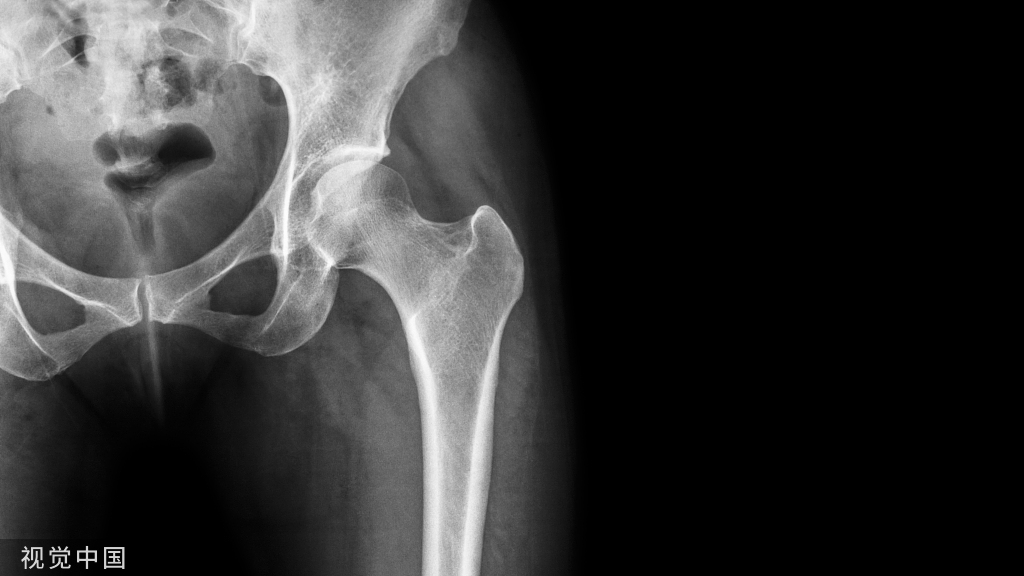

来,试试看。第一回合,住院治疗一个疗程,先缓解疼痛。4个月后复查:

尽管解决了疼痛问题,但复查时显示骨密度并没有太大的改变。